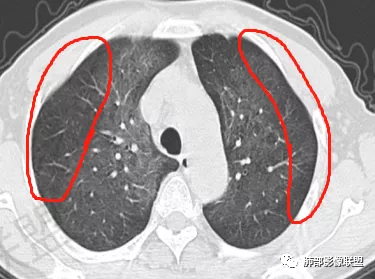

1、双肺从中心向外周对称性弥漫分布的磨玻璃密度影,无重力分布特点

2、中内带分布为主,胸膜下较少受累,可见月弓征

中期:孢子菌在肺泡腔内大量繁殖,引起炎性渗出及肺泡上皮增生,肺泡液内含有滋养体的嗜酸性渗出物及纤维蛋白和脱落的上皮细胞,Ⅱ型肺泡上皮细胞增殖修复受损的肺泡毛细血管间膜,肺间质内巨噬细胞、浆细胞和淋巴细胞增殖导致间质性肺炎,就是说有肺泡腔的密度增高,也有间质的增厚,整个肺受累区域密度都增高,形成以肺门为中心双侧对称的弥漫性磨玻璃样改变,胸膜下较少累及,呈典型的月弓征,采用积极的对症治疗后,大多数病变可吸收消失。

注意肺孢子菌肺炎的肺部影像看上去比较“干”,不会呈现重力趋势。肺血管影及支气管影都比较清楚,尤其是含气支气管影,常常会衬托得格外清晰。

结合患者症状典型的呼吸困难症状及影像学改变,临床症状轻,影像重,双肺从中心向外周对称性弥漫分布的磨玻璃影,无重力分布,胸膜下受累不明显(月弓征),呈典型的间质性改变,需要考虑肺孢子菌肺炎的可能,临床上需要结合有无HIV、使用免疫抑制剂病史、器官移植等免疫缺陷病史,还可以借助化验CD4细胞、LDH等进一步判断病情。